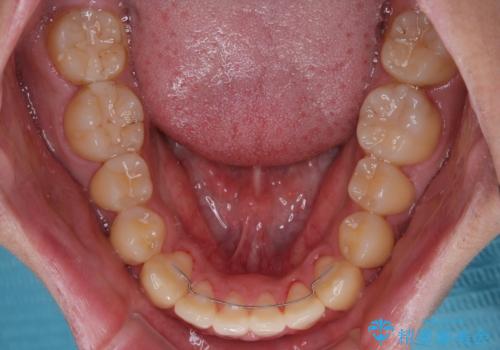

気になっていたクロスバイトは速やかに改善され、1年間で治療を終えることができました。

治療開始前は汚れが多く、全体的に歯肉が腫れていましたが、矯正治療を通して腫れも少しずつ改善されました。